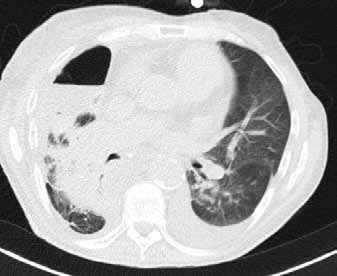

In der Klinik für Radiologie der Charité muss es oft sehr schnell gehen. Ganz gleich, ob Patienten mit Polytrauma, akutem Abdomen oder Schlaganfall eingeliefert werden: Die Klinik - mit mehreren Standorten über die Hauptstadt verteilt - bietet alle diagnostischen Möglichkeiten auf höchstem Niveau.

Die Klinik verfügt über 14 Computertomographen (CT), zwölf Magnetresonanztomographen (MRT) sowie zahlreiche Ultraschallgeräte. Allein am Campus Benjamin Franklin führen die Radiologen an sieben Tagen die Woche je zwischen 50 und 60 CT Untersuchungen täglich durch. Seit knapp drei Monaten steht ihnen dazu der neue 160-Schicht-Low-Dose-CT Aquilion PRIME zur Verfügung. Ein weiterer Aquilion PRIME sowie ein 640-Schicht-Volumen-CT Aquilion ONE ViSION EDITION wurden am Campus Mitte installiert. „Als wir nach einem neuen CT gesucht haben, war klar, dass dessen Ausstattung allen universitären diagnostischen Anforderungen gerecht werden muss", erklärt Dr. Stefan Niehues, Radiologe und Oberarzt der Klinik für Radiologie am Campus Benjamin Franklin.

„Mit dem neuen CT Aquilion PRIME können wir das komplette radiologische Spektrum der Charité abdecken. „Die gesamte Polytrauma-Diagnostik über die Akutversorgung bis hin zur Neuroradiologie und Diagnostik bei jungen Menschen führen wir mit dem Aquilion PRIME durch."

Dass sich Dr. Niehues und sein Team in einem langen und aufwendigen Entscheidungsprozess für das innovative CT aus dem Hause Toshiba ausgesprochen haben, hat mehrere Gründe. „Ich war Sofort beeindruckt von der Rechnergeschwindigkeit", sagt Dr. Niehues. Die Rekonstruktion der Bilder erfolge am Aquilion PRIME in einem Bruchteil der Zeit, die früher vergangen sei, bis das CT die komplette Bildserie samt Rekonstruktionen erstellte. „Heute haben wir alle Bilder nach wenigen Minuten", weiß Dr. Niehues, er hat das Intervall zwischen Untersuchung, Scan und Rekonstruktion aus Interesse selbst gestoppt. Früher sei das Polytrauma-Team samt Patient dann oft schon längst wieder verschwunden gewesen. „Die ständige Entscheidung zwischen schneller Rekonstruktion und einer kompletten Serie in dünnen Schichten und guter Bildqualität fand ich belastend - mit dem Aquilion PRIME hat sich das Problem gelöst", resümiert Dr. Niehues.

Neben der Rechnergeschwindigkeit lautet das Schlüsselwort bei dem neuen Gerät „Adaptive Iterative Dosis-Reduktion (AIDR 3D)". „Dieser mathematische Algorithmus erlaubt es uns, mit einem Bruchteil der Dosis zu arbeiten, die wir bisher für die erforderliche Bildqualität benötigt haben", weiß der Radiologe.

„Durch die Spitzentechnologie können wir bei gleich hoher Bildqualität die Dosis an Röntgenstrahlung bei vielen Untersuchungen auf ein Drittel reduzieren."